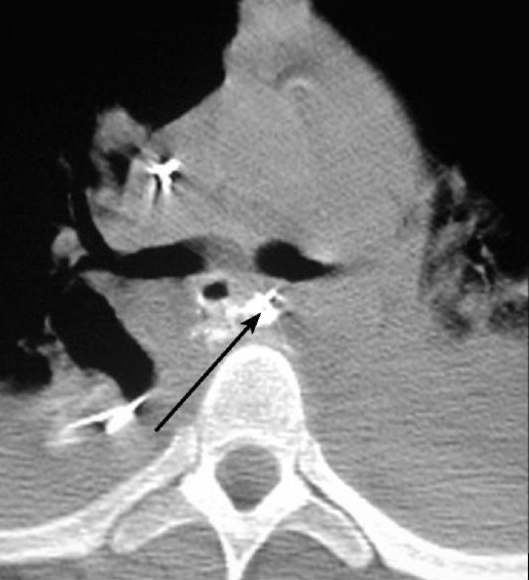

Şəkil 10. KT. Kontrastın qida borusundan ekstravazasiyası

Kəskin mediastinitin diaqnozunu dəqiqləşdimək üçün ən vacib müayinə KT-dir. KT-də divararalığında ödem, maye, hava, kontrast ekstravazasiyası mediastinitin xarakterik əlamətləridir.

- KT-də divararalığında ödem, maye, hava, bəzən də kontrast ekstravazasiyası (Şəkil 10)

Endoskopiyadan sonra emfizemanın ortaya çıxması, oral kontrastlı rentgendə və ya KT-də kontrast ekstravazasiyası qida borusu perforasiyasını göstərən əlamətlərdir (Şəkil 11).